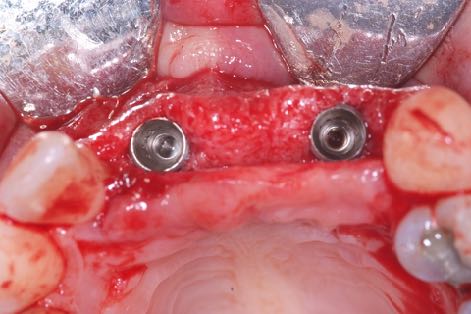

Plus important encore, on lit fréquemment que, pour augmenter artificiellement ce couple, il faudrait pratiquer une plus petite ostéotomie ou recourir à des techniques de compression osseuse. Or on dispose de plusieurs exemples dans la littérature qui prouvent que ces pratiques sont préjudiciables à la cicatrisation, risquent d’endommager l’os et de retarder le processus d’ostéo-intégration.

Il faudrait se concentrer sur la stabilité secondaire et l’obtenir le plus vite possible, en préservant en même temps la viabilité et la stabilité de l’os péri-implantaire, pour assurer la réussite clinique de l'implant à long terme.

Je suis convaincu que le maintien de l’os marginal péri-implantaire est l’un des facteurs clés de prévention des complications biologiques futures. Par conséquent, si l'on arrive à obtenir une stabilité secondaire en minimisant les lésions osseuses au niveau cellulaire, les conditions d’une réussite prévisible durable sont presque entièrement remplies.